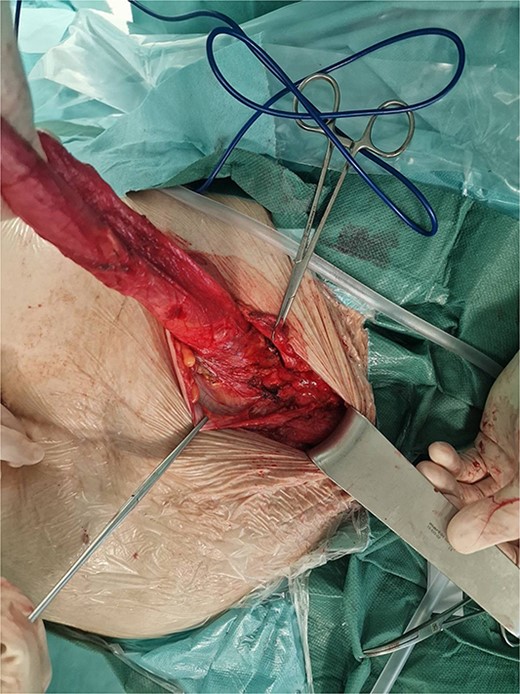

Surgery was planned with general anesthesia. Preoperative bowel preparation was not conducted in this case. The patient was set in a slight Trendelenburg position. As soon as an intravenous muscle relaxant was given as a part of the general anesthesia protocol, successful manual hernia reduction was performed and the defect became easily detectable. A left inguinal approach was decided to be performed. The hernia sac was visible after the left inguinal canal was opened, and its dissection was not technically demanding. The left uterine round ligament was resected and the hernia defect was defined as a direct (Fig. 3). The hernia sac was reduced and a standard Lichtenstein repair followed. A plastic surgeon excised the skin that used to cover the giant hernia. A subcutaneous suction drain was inserted (Fig. 4). Operative time was 75 minutes. In the postoperative period, local wound cellulitis with fever occurred and was treated with intravenous antibiotics (5 days of duration) and daily wound dressings. The hospital stay was 5 days.